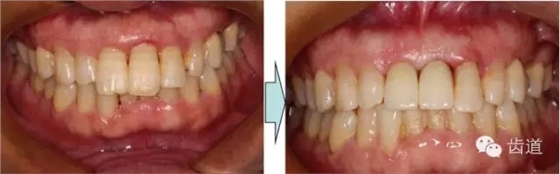

治療前后對(duì)比

戴牙一年前后對(duì)比